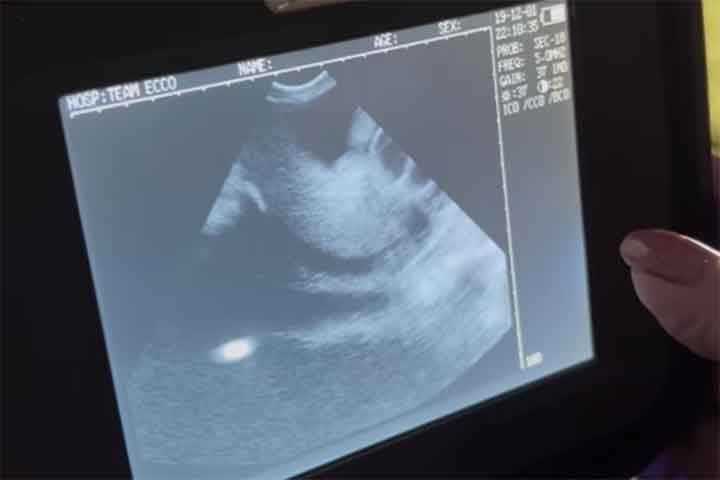

Arraia engravida sem contato com macho da espécie